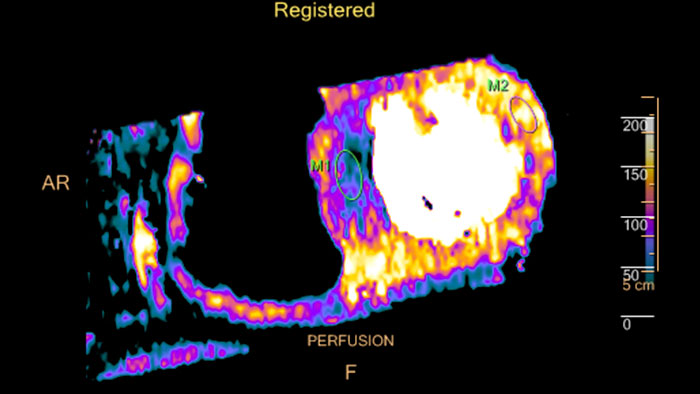

CT-MI Fusion

Fusing cardiac CT-MI images

Cardiac CT-MI Fusion incorporates support for myocardial perfusion imaging (MPI).

Benefits

- Allows loading both gated and un-gated rest, and gated and

un-gated stress MI datasets simultaneously with the CT. - The MI images are displayed in the short axis and the two long axis planes.

- The axes definition is derived from the CT study.

CT Dynamic Myocardial Perfusion (DMP)

Dynamic color maps provide an assessment of myocardial risk

Provides automatic and manual tools to help visualize and assess signal intensity differences (in Hounsfield Unit) focusing on the left ventricular myocardium, providing quantitative myocardial perfusion measurements for CT images.

Benefits

- Supports axial, ECG-gated CTA images, consisting of multiple time shots within the same acquisition of the myocardial region over time (i.e. dynamic CT scans), after an injection of intravenous contrast.

- Automatic and manual tools providing quantitative myocardial perfusion parameters such as: Peak Enhancement, Time To Peak, Perfusion and Blood Volume, and provides color maps representation of the results and graphical representation of intensity curves.